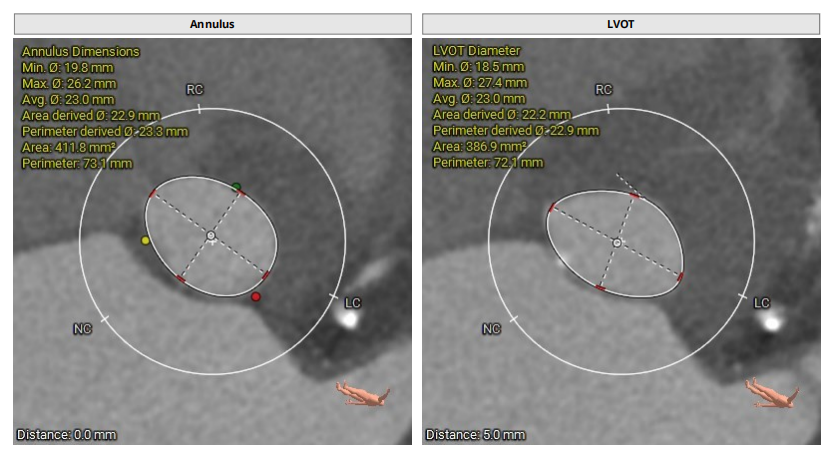

CT提示

主动脉根部:

三叶瓣,轻度钙化,法式窦结构尚可,左冠开口高度约15.3mm,右冠开口高度约17.1mm,STJ高度约22.6mm、直径约28.8mm,升主动脉未见明显扩张,心脏角度约42°,左室形态大小可,左冠切线位:LAO40° CRA9°,右窦居中位:LAO34° CRA3°,左右重叠位:LOA4° CAU23°。